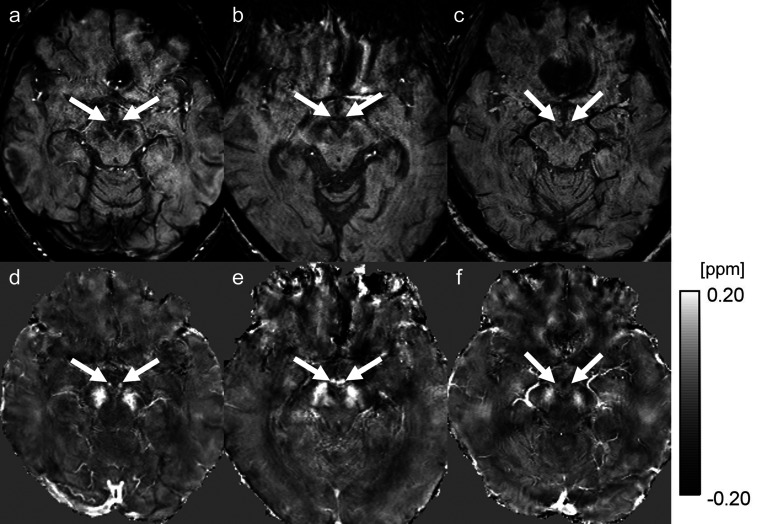

众所周知,乳腺体(MMB)内出血是韦尼克脑病的症状之一。两名韦尼克-科萨科夫综合征(WKS)患者的脑磁共振成像通过使用定量易感性图谱(QSM)显示了代表乳腺体内血色素沉积的高易感值。在诊断WKS时,QSM为感度加权成像提供了额外的感度值信息。

Hemorrhage inside the mammillary bodies (MMBs) is known to be one of the findings of Wernicke encephalopathy. Brain MRI of two patients with Wernicke-Korsakoff syndrome (WKS) demonstrated high susceptibility values representing hemosiderin deposition in MMBs by using quantitative susceptibility mapping (QSM). QSM provided additional information of susceptibility values to susceptibility-weighted imaging in diagnosis of WKS.